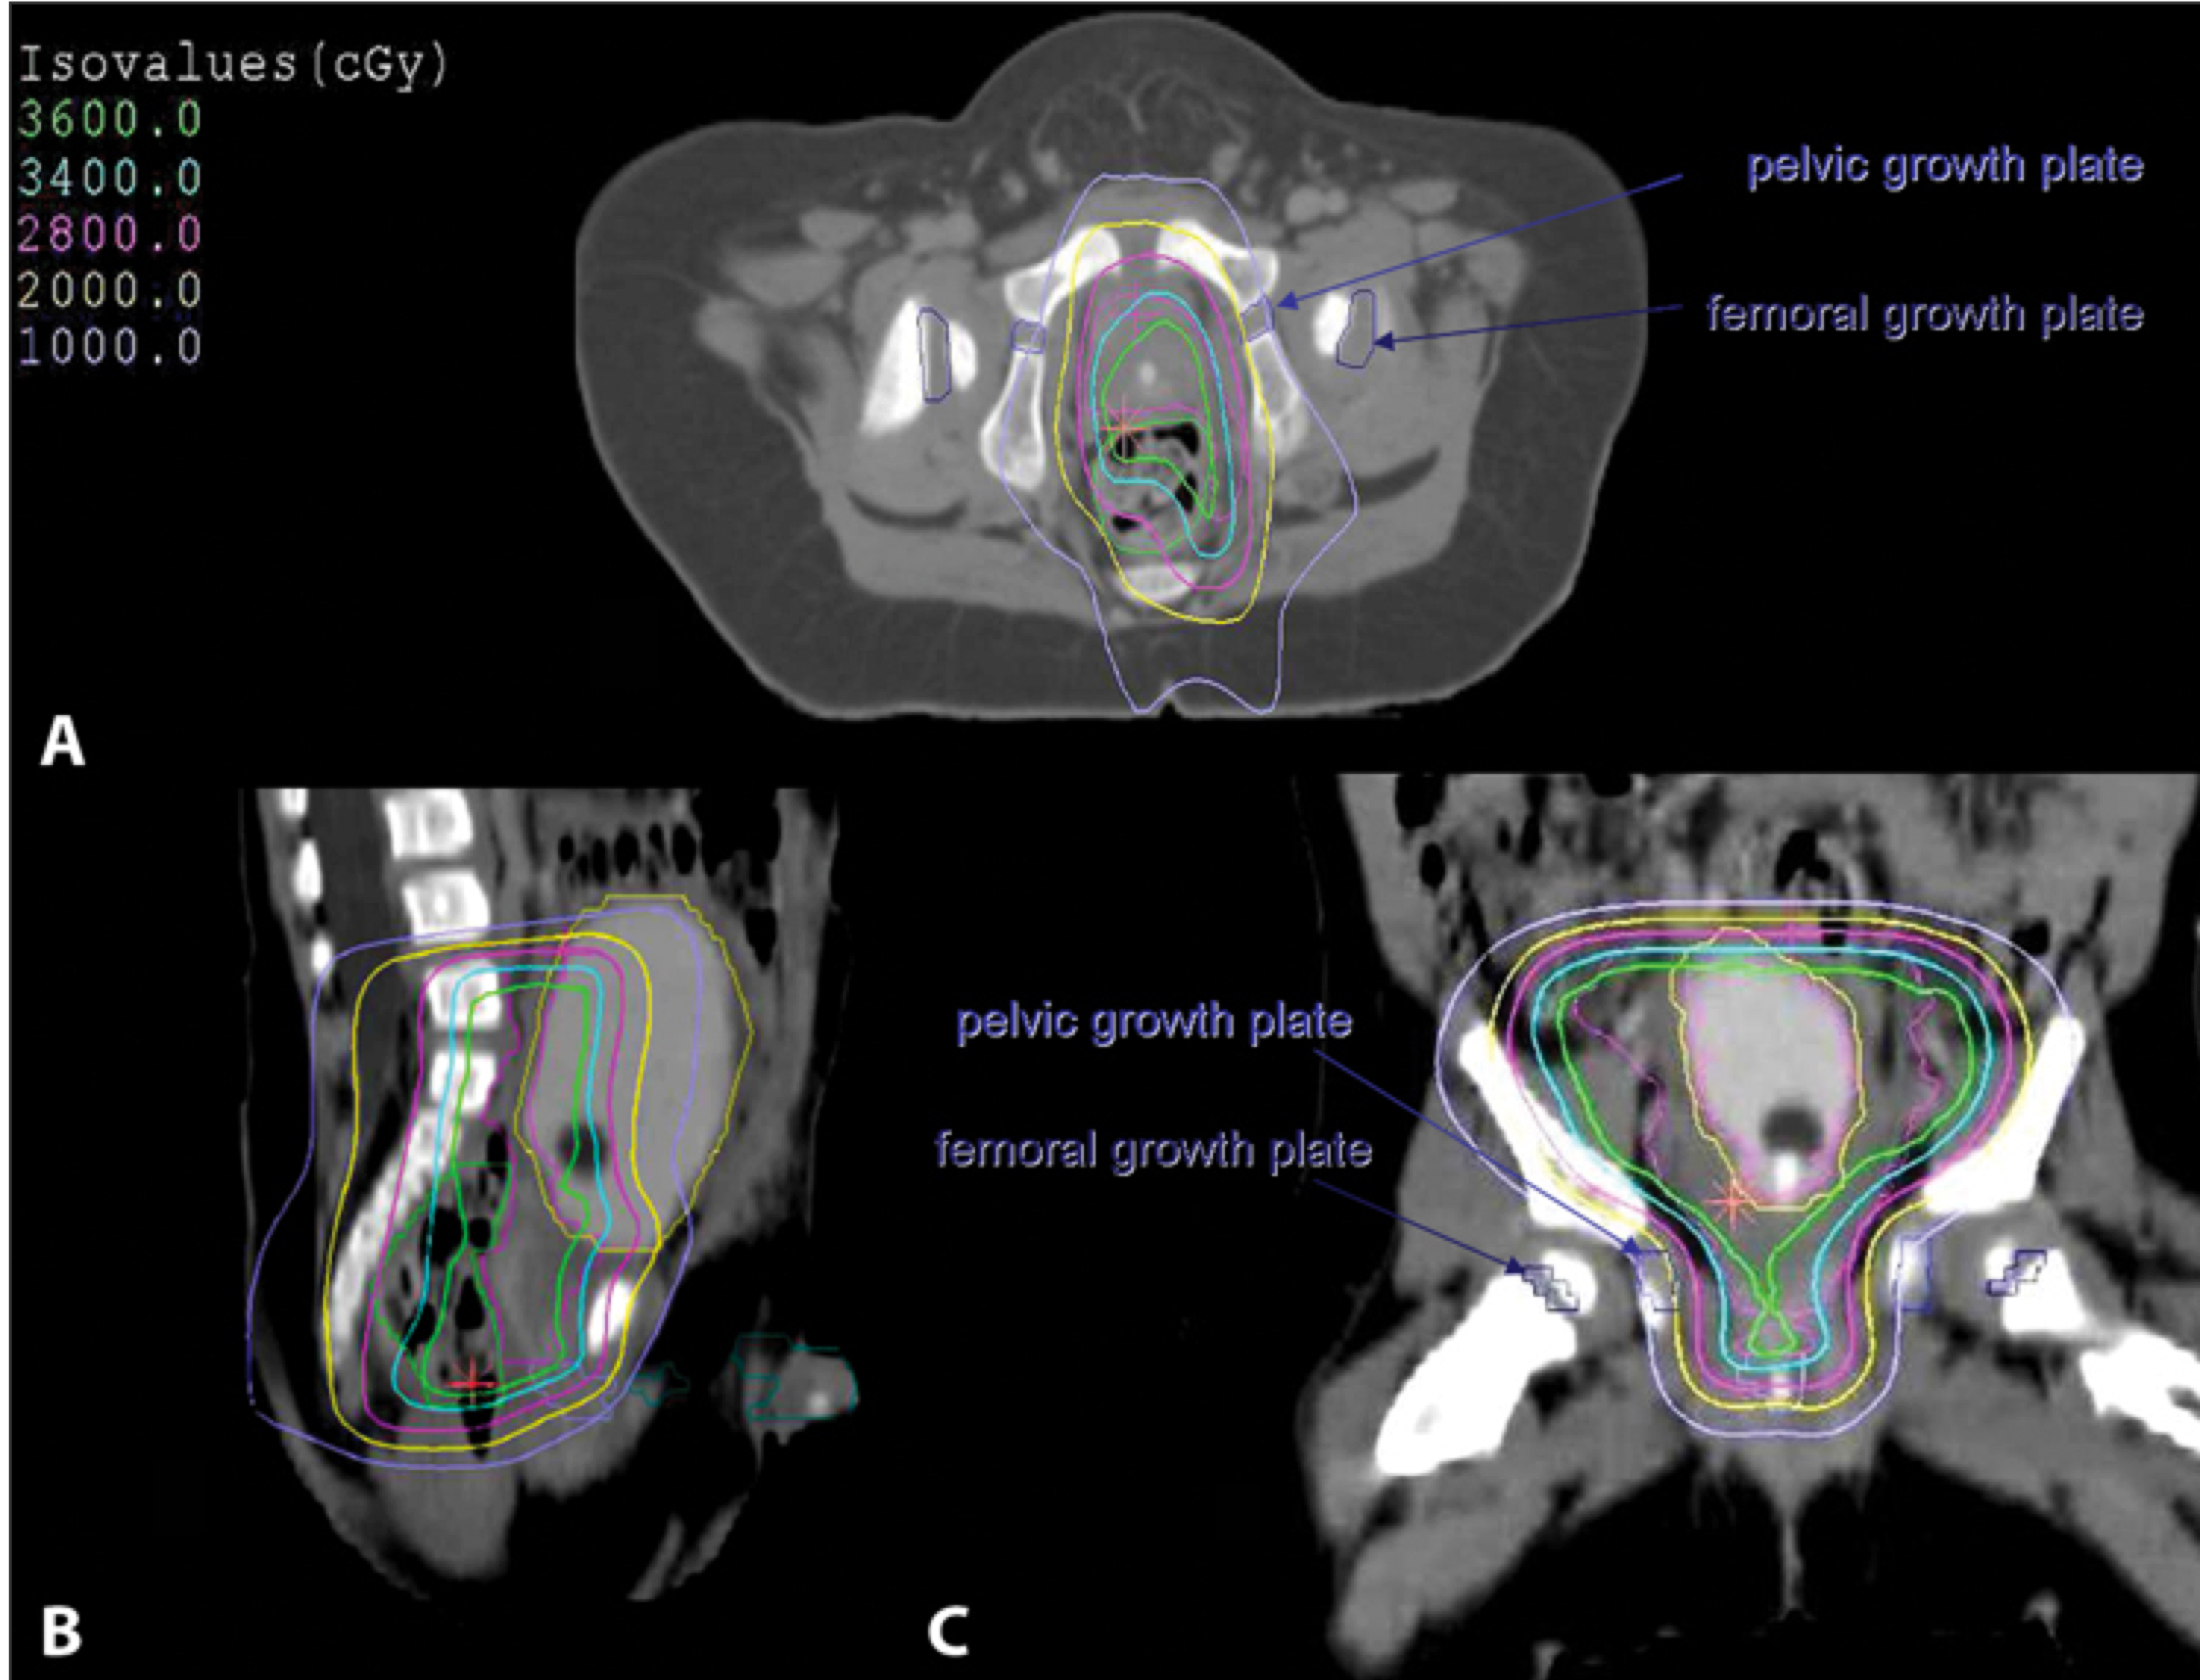

Radiation Therapy Treatment Planning And Techniques

3D conformal treatment planning is essential. CT (for boney anatomy and growth plate identification) fused with MRI (for soft tissue identification) provides the best imaging technique. For patients with large tumors displacing bowel GTV is defined as the preoperative tumor volume excluding the debulked portion while accounting for shifting structures.

Critical structures are:

• bladder

• rectum

• bowel

• pelvic and femoral head growth plates (keep dose < 10-20Gy)

• penile bulb and testes

IMRT may be disadvantagous over 3D crt due to the larger volume of low dose irradiaiton which may increase the risk for second malignancies.

Isodose volume for microscopic residual disease RMS of bladder to 36 Gy. Pelvic growth plates get 6-20 Gy (RBE) and femoral growth plates < 3 Gy.